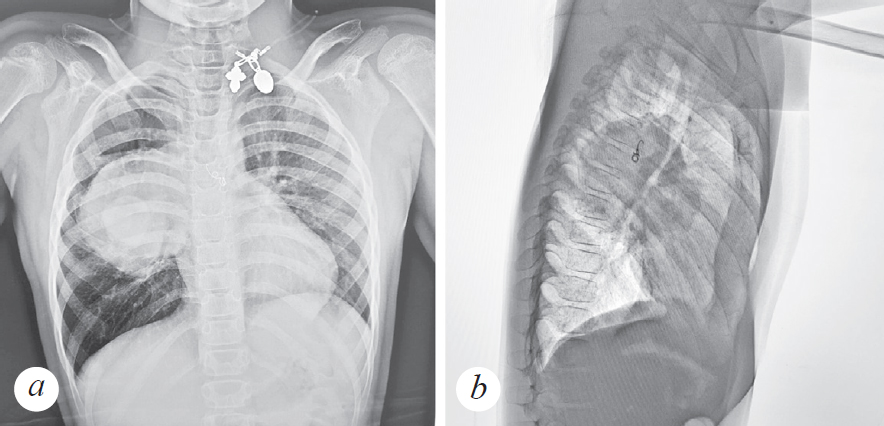

The authors bring to the attention of colleagues a description of a clinical case of pleuropulmonary blastoma in an 8-year-old child, diagnosed against the background of an acute respiratory viral infection. He fell ill acutely with a rise in temperature and an unproductive cough. The condition was regarded as a course of an acute respiratory viral infection, symptomatic therapy was carried out. After 8 days from the onset of respiratory viral infection, there is a sharp deterioration in the condition in the form of shortness of breath, refusal to eat and drink, and weakness. The child is hospitalized in a Central District Hospital, differential diagnosis with pneumonia is carried out. According to the examination (plain radiograph and CT scan of the chest), a large volumetric formation with even contours is visualized in the right lung. The patient is transferred to a specialized hospital in St. Petersburg. After an MRI of the chest organs with contrast, taking a biopsy material and performing a histological examination, the patient was diagnosed with a tumor of the right lung — pleuropulmonary blastoma type II.